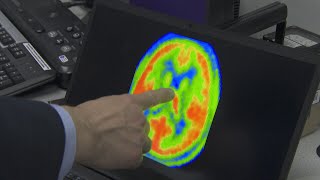

Symptoms from COVID-19 linger for some, may impact brain

COVID 19: Lingering and Chronic Symptoms After Recovery from Coronavirus Infection Brain inflammation found in some patients with long COVID

Brain inflammation found in some patients with long COVID Why Do Coronavirus Symptoms Linger For Some Survivors? | Sunday TODAY